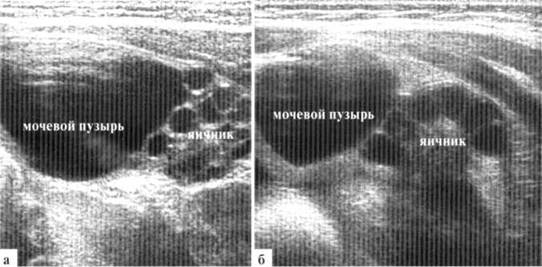

Количество фолликулов в яичниках новорожденных может быть различным, достигая 10 и более в одном скане, при этом дальнейшее половое развитие девочек в течение первого года жизни протекает без особенностей. Такие мультифолликулярные яичники относительно часто наблюдаются у девочек, которые находятся на грудном вскармливании, что позволяет предположить роль материнского гормонального фона (рис. 1.2).

Рис. 1.2. Гиперстимулировнные яичники новорожденной: расположены высоко, рядом с боковой стенкой мочевого пузыря, по размером яичник сопоставим с мочевым пузырем